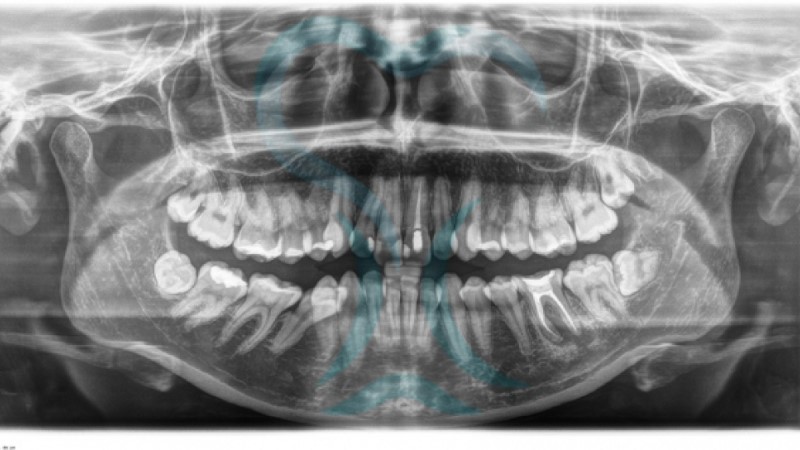

Radiografías Intra/ExtraOrales